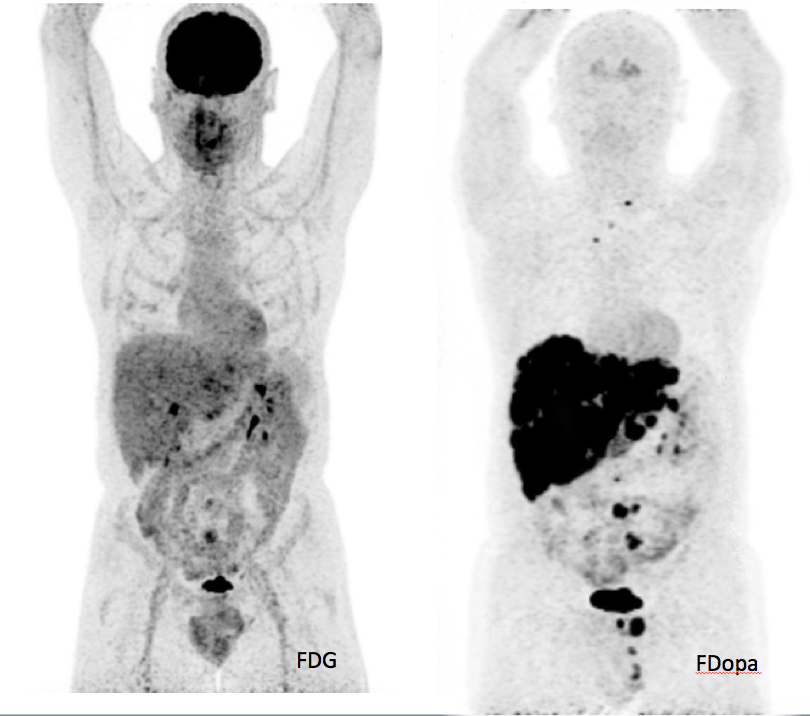

在核医学领域,人们使用核反应堆和粒子加速器生产地球自然界中不存在的放射性物质(这些人造放射性物质的半衰期很短,只有几天甚至几小时)。这些物质非常重要,可用于诊断成像(如PET成像使用放射性元素氟-18;闪烁扫描术使用锝-99)和放射治疗(如用于治疗甲状腺癌的碘-131)。

PET(正电子发射型计算机断层显像技术)成像图。PET通过使用放射性元素氟-18标记葡萄糖(左图)或标记多巴胺(右图),实现显像。[3]